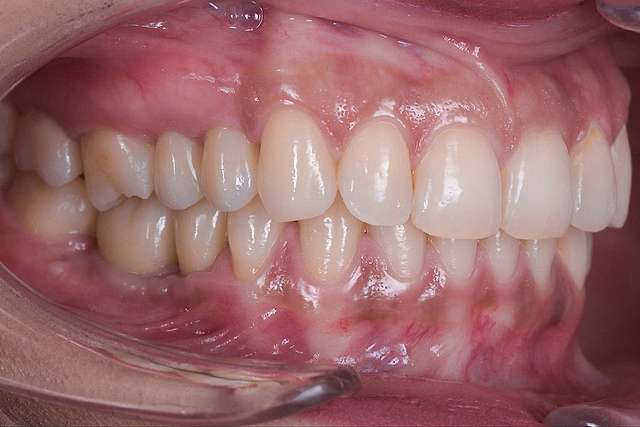

Guided surgery, for one, facilitates an ideal pre-planned position, in relation to available bone, and even more important, in relation to the future implant supported crown. Guided surgery translates into increased precision, which means safer surgeries, reduced surgery time, and reduced trauma. Also the focus of these types of treatments is shifted towards tissue reconstruction, which on the long run, has a far greater impact esthetically and biologically. Tissue stability means implant longevity. This case is a relevant example for this type of approach towards implant dentistry.